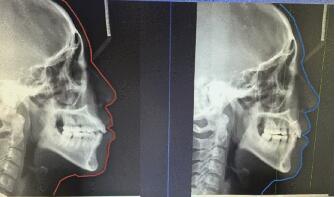

3、側(ce) 位片:在牙齒正畸的時候使用比較多,通常還有正位片、側(ce) 位片之分,主要是可以通過牙片來查看牙齒於(yu) 頜骨的大致情況,便於(yu) 正畸醫生製定合適的矯正方案。價(jia) 格通常也在一兩(liang) 百左右。如下圖:

側(ce) 位片